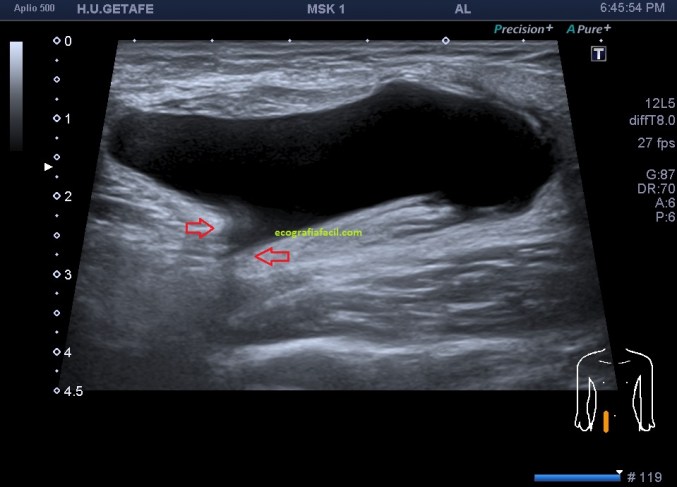

En el caso que te traigo hoy no hizo falta buscar mucho, nada más poner la zona en corte transverso en la región inguinal derecha, cerca de los labios mayores, la paciente tenía una masa blanda, ligeramente dolorosa durante la exploración que había aumentado ligeramente tiempo atrás y que ecográficamente tenía un aspecto anecoico,imagen 1, de paredes finas, más grande en su eje lateral que en el eje antero posterior y que se deformaba con la ligera presión del transductor y que no modificaba su ecoestructura con la maniobra de Valsalva.

En cuanto localicé este hallazgo realicé corte transverso (imagen 2) y longitudinal (imagen 1), con medidas y estudio en modo doppler para ver vascularización (imagen 3, flecha amarilla), seguidamente, era muy importante asegurar algunas referencias locoregionales como los grandes vasos femorales, siempre debemos documentar esta coexistencia y buscar un cuello que puedes observar con las dos flechas rojas de la imagen 1 y que la ecoestructura marca perfectamente al ser anecoica.